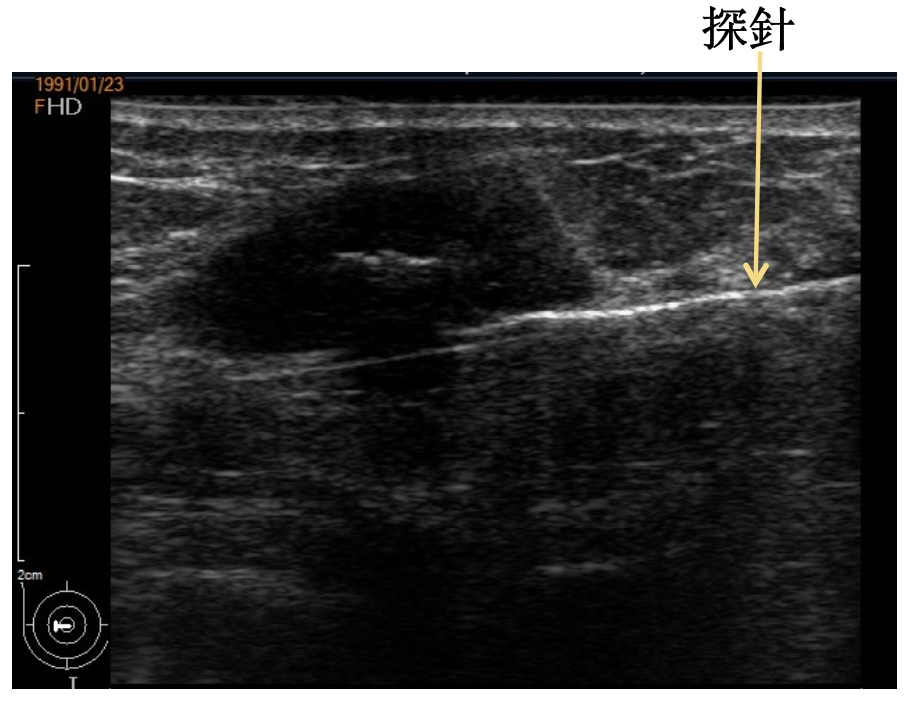

於乳房表皮劃開 0.3~0.5 公分切口,在超音波導引下插入探針,探針透過真空輔助,在超音波導引下取出(腫瘤)組織。

3. 超音波定位及引導之下,透過真空輔助抽吸取出腫瘤組織